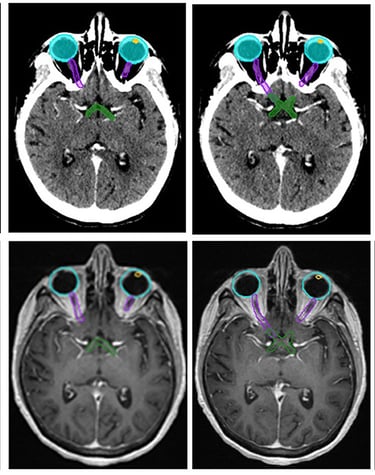

Gallery

Snapshots from patient journeys and expert insights